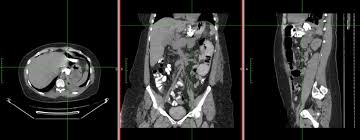

Coronal Plane Of Abdominal Mdct In A 54 Year Old Woman Prepared With Download Scientific Diagram